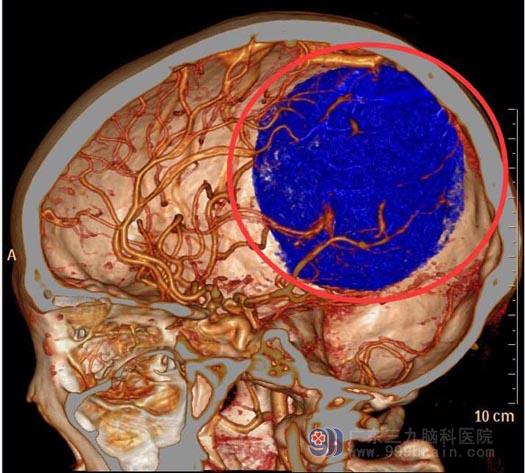

金姐六天前向左侧转头时出现头痛,以后枕部为主,休息后可缓解。当地医院头颅CT检查结果:右侧顶枕部巨大占位,考虑脑膜瘤。头颅MR检查提示:右侧枕顶部较大占位性病变,直径约7.2cm,考虑脑膜瘤可能性大。头颅CTA检查提示:右侧枕顶部占位性病变,血供丰富。

▲术前CTA